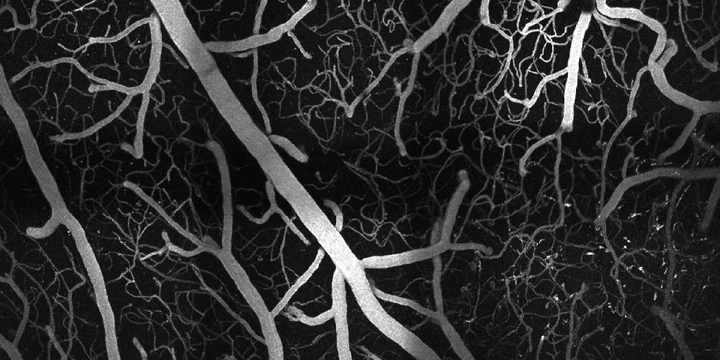

Two-photon maximum intensity projectionMultiphoton microscopy is a powerful in vivo imaging technique because of its ability to image in three dimensions at high resolutions. It is made possible by a nonlinear dependence on excitation intensity, which localizes the resulting signal to the focal volume of the excitation light. Unlike conventional fluorescence microscopy, which requires a single photon to excite a fluorophore, multiphoton microscopy requires two (or three) photons with longer wavelengths to generate fluorescence. These longer excitation wavelengths allow multiphoton microscopy to achieve imaging depths significantly greater than confocal microscopy.

We design and build custom two- and three-photon fluorescence microscopes to study the complex vascular and neuronal structures of the cerebral cortex in mice. We also use two-photon phosphorescence lifetime microscopy to precisely measure oxygen concentrations in the neurovasculature. These systems allow us to visualize the cortex at depths and resolutions pushing the limits the optical imaging.